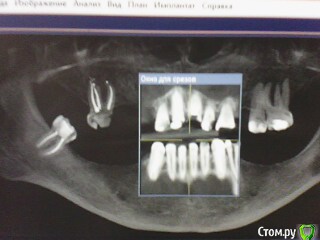

ОльгаS Опубликовано 16 декабря, 2014 Автор Поделиться Опубликовано 16 декабря, 2014 (изменено) Будет удален передний корень, где сломан штифт, и верхняя правая шестерка - под вопросом, но сама склоняюсь к тому, что бы ее сохранить, один их предложенных мне специалистом вариантов - 2 импланта, верхняя челюсть, и 4 - нижняя, в другой клинике предложили, удалить шестерку, тогда 3 импланта - верхняя, и 5 - нижняя, какой вариант все же более оптимален, мне самой, естественно, не определиться, да и как, если один специалист заявил, что слева в нижней челюсти близко расположен челюстно-лицевой нерв и имплант он там ставить не будет, а установит два и сделает один зуб подвесным, т.е. будет мостик, клиники обе - бизнес-класса. Изменено 16 декабря, 2014 пользователем ОльгаS Ссылка на комментарий

Doc Опубликовано 16 декабря, 2014 Поделиться Опубликовано 16 декабря, 2014 Проблема в том, что специалисты, к которым обратилась в реале имеют разное мнение:По этим двум скриншотам на форуме будет еще больше разных мнений. Нужны либо более качественные снимки, либо личная консультация у имплантолога и ортопеда вместе. Ссылка на комментарий

ОльгаS Опубликовано 16 декабря, 2014 Автор Поделиться Опубликовано 16 декабря, 2014 Оба раза на консультации присутствовали и имплантолог и ортопед, добавлю еще снимки: Ссылка на комментарий